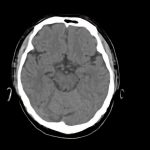

下垂体腺腫

断層撮影

手術前1

手術後

No.’15_2 手術前1

No.’15_2 手術後